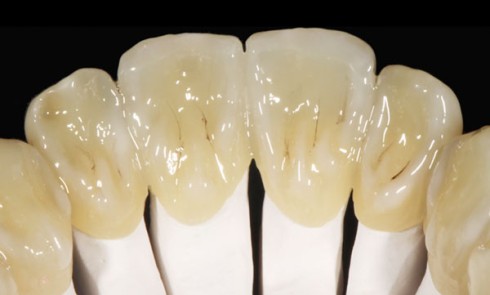

Article réservé à nos abonnés Paramètres essentiels pour la réalisation d’une prothèse céramo-céramique sur zircone

Dans la première partie de cet article [1], nous avons présenté l’historique et l’évolution du matériau zircone, les composants en...